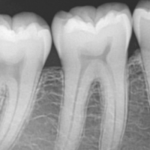

Periapical

Forma parte de las radiografías intraorales. Su objetivo principal es ver los ápices dentales, la punta de las raíces, la corona, el tejido óseo y alrededor de los dientes. Gracias a esta técnica se puede explorar de manera exhaustiva todo el diente y a su alrededor.